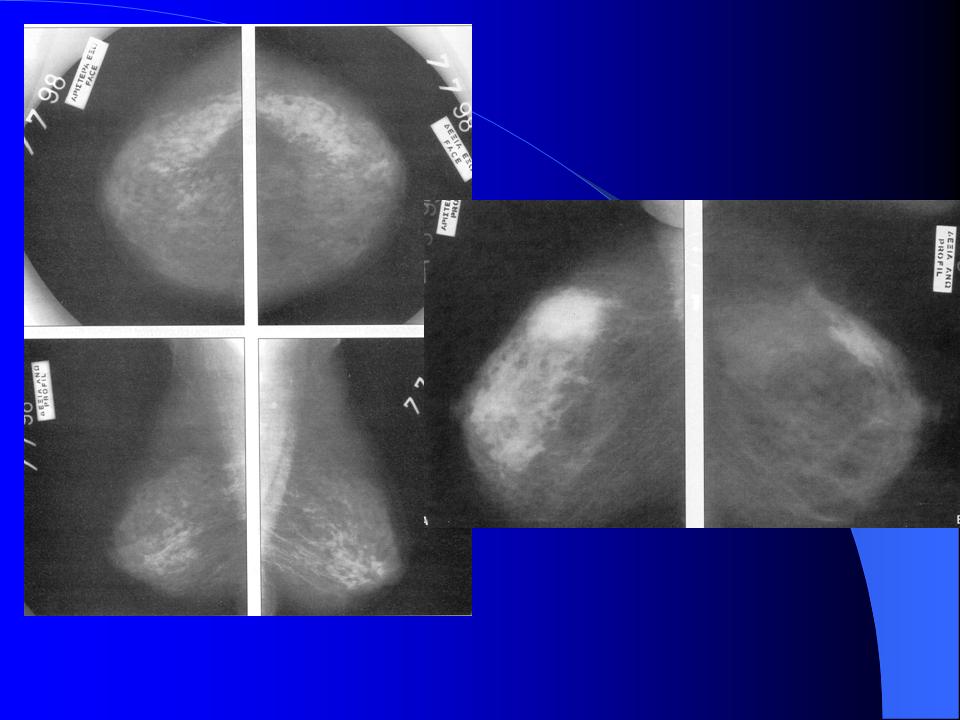

Χειρουργικές Παθήσεις Πάθηση Μάστου - ΚΑΛΟΗΘΕΙΣ ΠΑΘΗΣΕΙΣ ΜΑΣΤΟΥ ΣΥΓΓΕΝΕΙΣ ΑΝΩΜΑΛΙΕΣ ΤΩΝ ΜΑΣΤΩΝ - ΕΠΙΚΤΗΤΕΣ ΒΛΑΒΕΣ ΤΟΥ ΜΑΣΤΟΥ